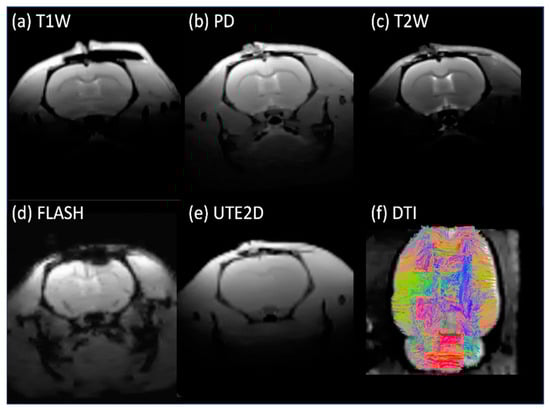

The in vivo rat brain imaging at 9.4 T did not exhibit appreciable signal loss adjacent to the PTFOS electrodes in the anatomical images when using the T1W, T2W, PD, FLASH, and UTE sequences (Figure 8). The signal loss on top of the brain in the FLASH image was due to the high sensitivity of the imaging sequence (FLASH) to the susceptibility mismatch induced by the surgical procedure, but not because of the PTFOS device. We also obtained good diffusion tensor fiber tracks in the PTFOS rat images while the connector was present. Compared to the rat with sham implantation, neither the sham Gelfilm nor the PTFOS grid introduced appreciable artifacts to the images at 9.4 T. To assess the impact of the PTFOS electrodes on imaging quality, we examined the SNR in the T2-weighted images. Figure 9 and Table 4 showed comparable SNRs among the sham and PTFOS implantations, in both the brain and the entire imaging volume. For fMRI, the minimal distortion observed in the EPI images in the PTFOS and sham rats apparently resulted from the tissue trauma introduced by the implantation procedure, not because of the PTFOS device. We were able to obtain reasonable fMRI activity readings in response to forepaw stimulation (2 Hz/1 mA) of the rat with the PTFOS implantation (Figure 10).

Figure 8. In vivo images of the rat with the PTFOS and connector implanted at 9.4 T, showing only minimal artifacts near the electrodes.

These artifacts, or ‘blind spots’, are especially problematic in fMRI with echo-planar imaging (EPI), which is particularly sensitive to magnetic susceptibility. While these artifacts might not hinder the identification of functional activity in brain areas far away from the electrodes, they significantly obstruct the mapping of local responses near the electrode site. This leads to incomplete and biased activation pattern mapping, particularly affecting those areas near the electrode tracks. This study focuses on developing ECoG grids using polymer-thick film (PTF) deposited on an organic substrate (PTFOS, Figure 2a). This approach aims to ensure safety during MR imaging and produce artifact-free images [2]. Previous research has shown that PTF-based EEG caps can provide artifact-free MR imaging and high-quality EEG recording, setting a precedent for applying this technology in ECoG [3,4,5]. The proposed design includes thin, flexible grids that conform to the brain’s surface, potentially reducing post-surgical complications and improving recording placement. The PTFOS grids underwent testing to evaluate MRI heating and the presence of imaging artifacts. The development of PTFOS grids represents a significant advancement in ECoG technology, addressing previous limitations and offering a safer, more effective tool for preclinical research. This research builds upon our earlier findings, published in Radiology [2], demonstrating that the PTFOS technology remains artifact-free even at higher MRI fields, specifically at 9.4 teslas (T) compared to the 7 T previously studied. Moreover, while our earlier research focused solely on post-mortem imaging [2], this study extends our scope by examining MR images of live rats with implanted PTFOS devices, using various MRI techniques. The focus of this manuscript is to demonstrate that the new PTFOS implantation provides usable MR images, in contrast to the distorted images produced by traditional ECoG devices that lead to disturbances in magnetic field homogeneity. We tested image quality with PTFOS implantation using various clinical MRI sequences with different sensitivities to magnetic field homogeneity, including T1-weighted (T1W), proton density (PD), T2-weighted (T2W), fast low-angle shot (FLASH), ultra-short TE (UTE), diffusion tensor imaging (DTI), and functional MRI (fMRI). The conventional spin-echo-based sequences, including T1W, PD, and T2W, are typically insensitive to magnetic field inhomogeneity, whereas the FLASH sequence, a steady-state conventional sequence, as well as EPI and DTI sequences, are typically sensitive to field inhomogeneity [6].